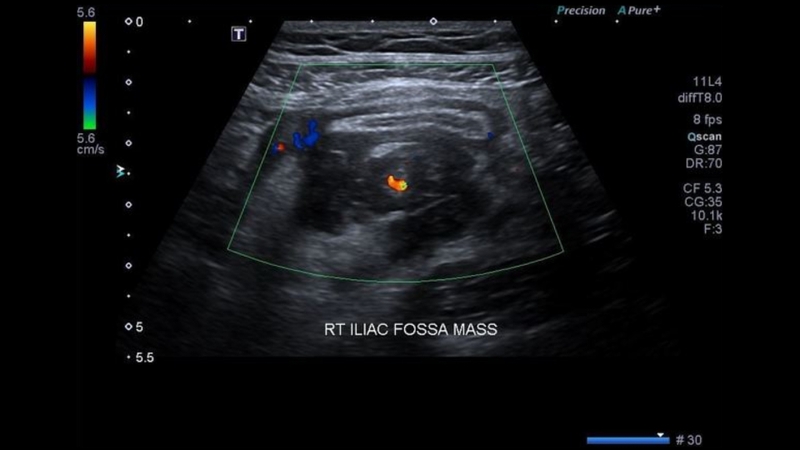

Áp xe ruột thừa

Trường hợp viêm ruột thừa tiến triển thành áp xe, siêu âm có thể ghi nhận:

• Khối áp xe có hồi âm kém hoặc hỗn hợp, có thể chứa hơi và được bao quanh bởi giới hạn rõ ràng.

• Nếu ruột thừa bị hoại tử hoàn toàn và không còn nhận diện được trên siêu âm, dấu hiệu quan trọng nhất là sự hiện diện của sỏi ruột thừa trong ổ áp xe.

Hình ảnh viêm ruột thừa cấp trên siêu âm như thế nào? 4

Hình ảnh siêu âm viêm ruột thừa tiến triển thành áp xe